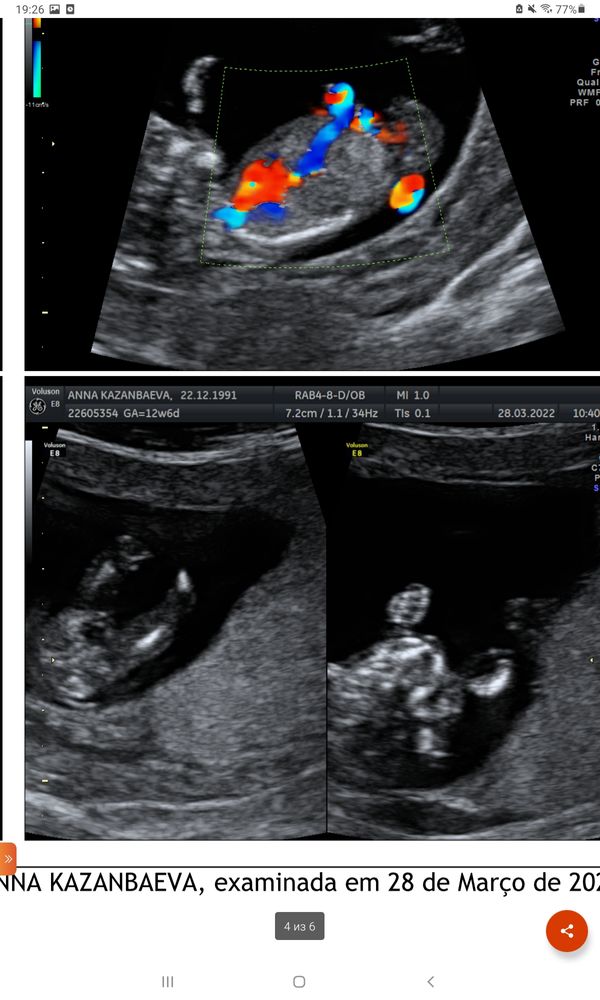

Мальчик или девочка?🙏❤🙂

Изображение На мальчика похоже. Сейчас покажу как у меня, сказали девочка...

Узнать пол по крови Половой бугорок